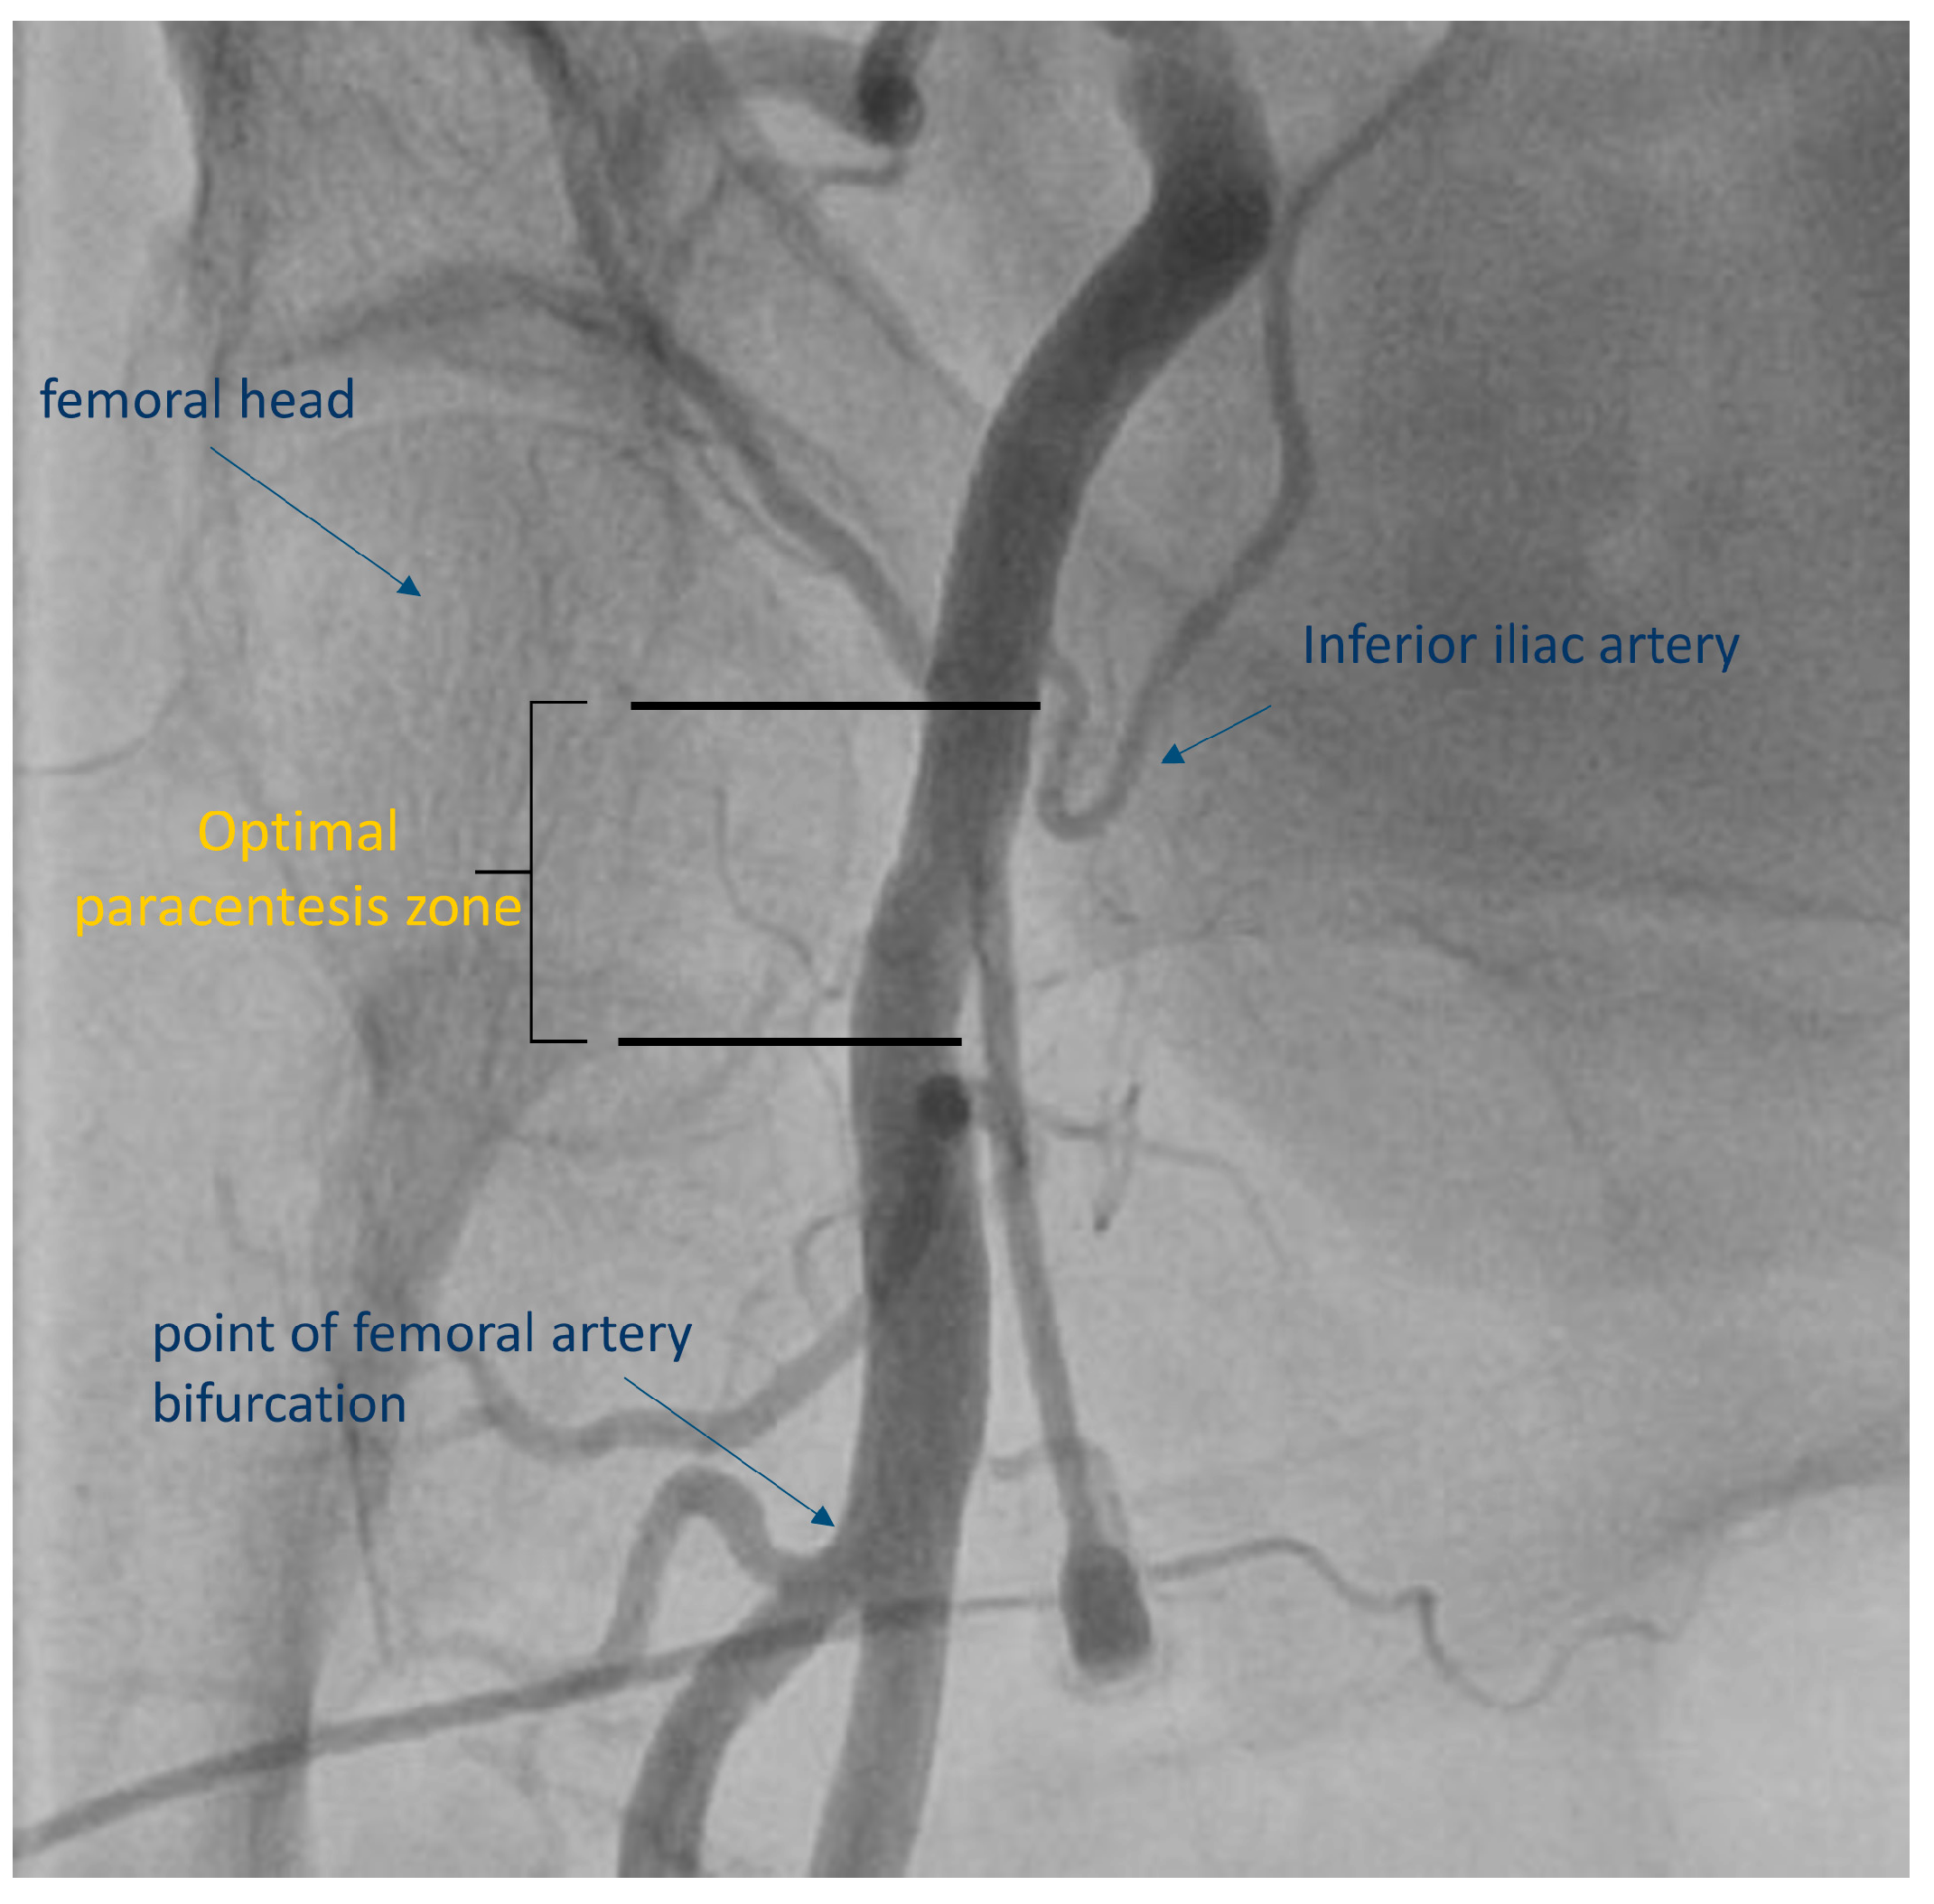

2. Existing Evidence Supporting the Use of Ultrasound-Guided Femoral Access